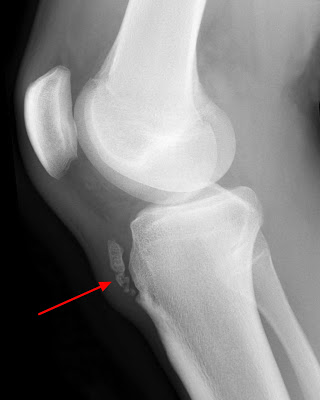

DISTORSIONE ALLA CAVIGLIA: STRATEGIE DI INTERVENTO

DISTORSIONE ALLA CAVIGLIA: FISIOPATOLOGIA E FATTORI DI RISCHIO